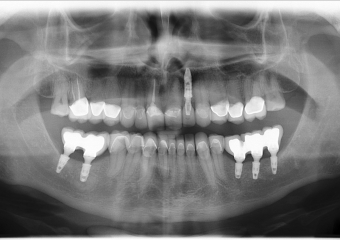

Raio - x inicial em 2014

Implantes instalados, em Setembro de 2014